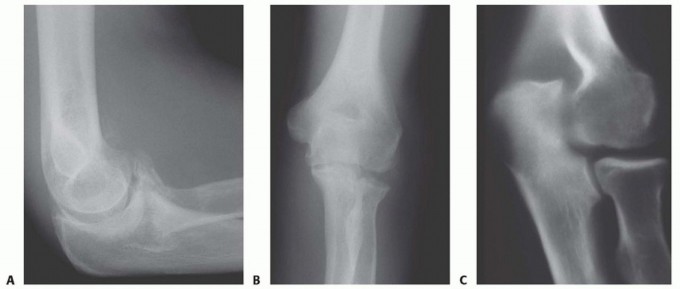

15 MIN READ Surgical Management of Traumatic Conditions of the Elbow: Interposition Arthroplasty يناير 2023 Read More